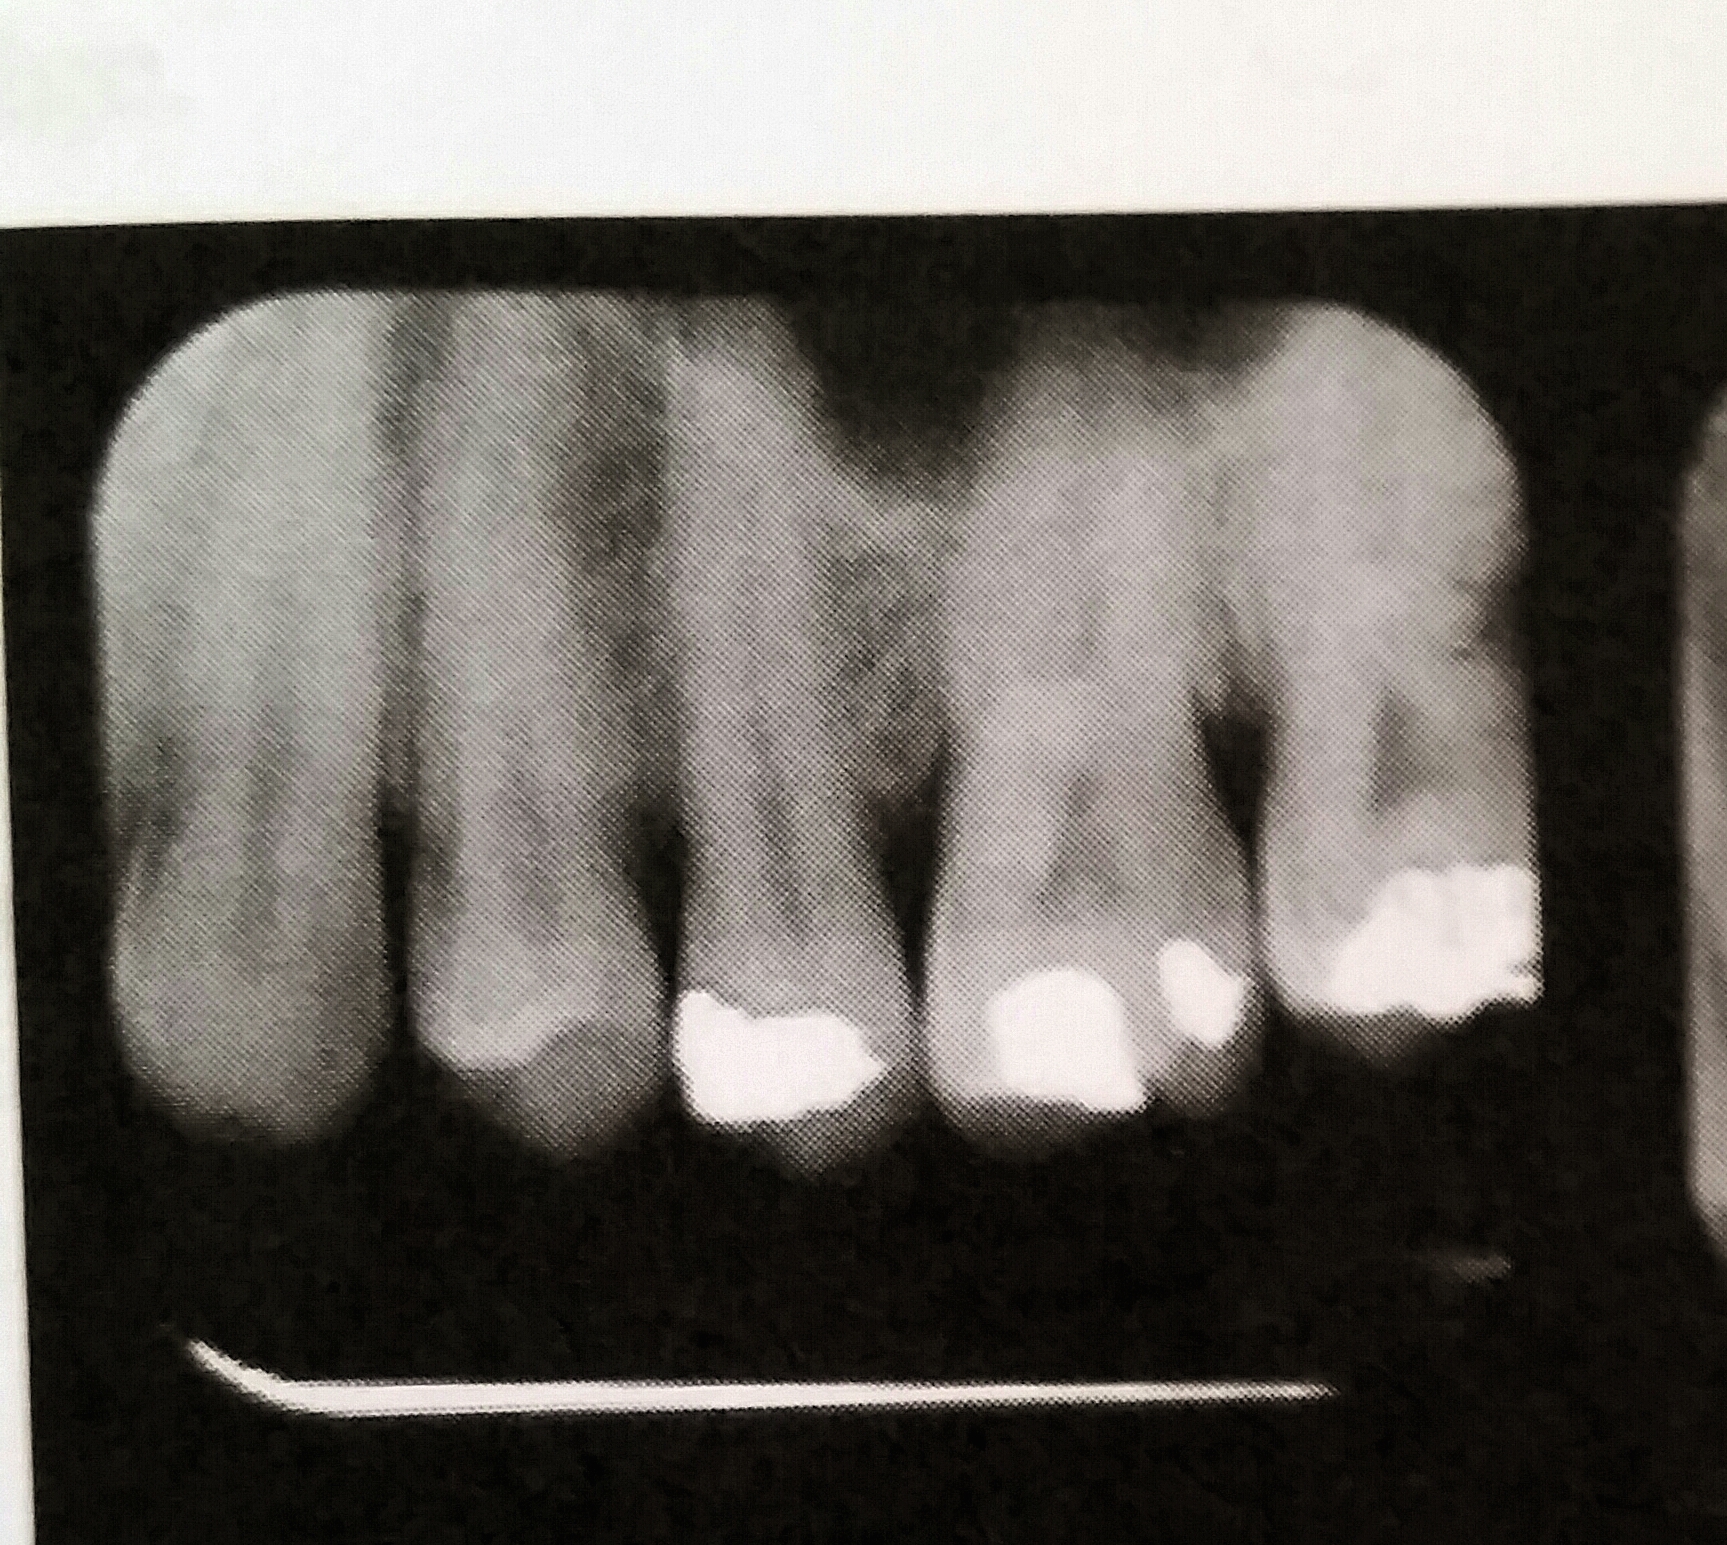

Reversed Film Dental X Ray . This combination of a light film with the characteristic pattern indicates that the film packet was exposed backward in the patient’s. Incorrect exposure can be caused by many factors; Backward placement of a film in the mouth causes the lead foil inside the packet to face the radiation source instead of the film directly. Table 5 lists various errors that can occur with panoramic imaging. Reversed film refers to a film exposed from opposite side. Film type receptors are manufactured with different film speeds, which determines the amount of radiation exposure required to produce a radiograph of standard density. The most common being improper exposure settings. Reverse film placement results when the beam passes through the lead foil backing before it strikes. It is important for the clinician to be able to understand errors when they occur and how to correct them.